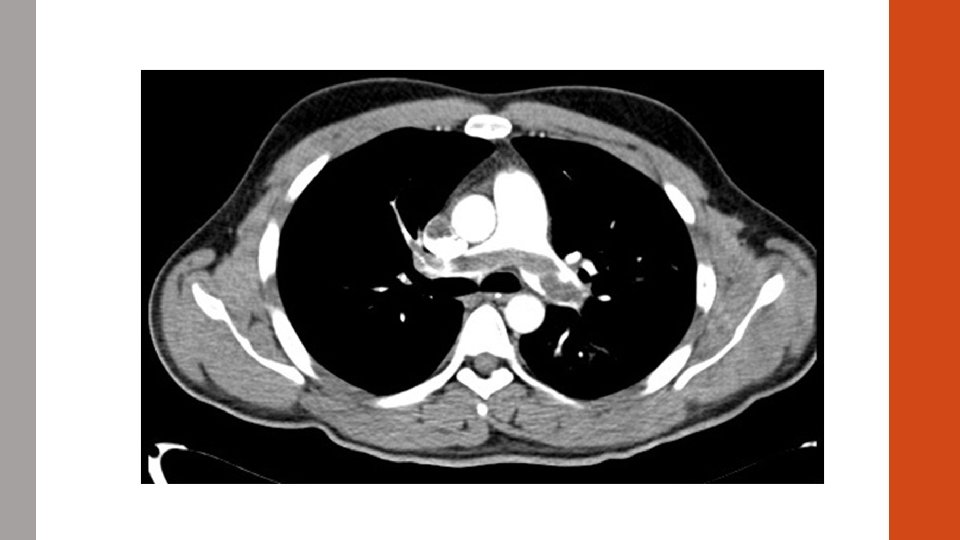

#5 CASE STUDY A 31 year old smoker presents to the ED with acute onset shortness of breath. Symptoms began ~2 hours prior to arrival. Syncopal event en route. She also endorses chest pain. T 98. 0 HR 125 BP 90/55 Sp. O 2 85% on 6 L NC.

A R L B

ABG 7. 56/20/56/24 p. H/CO 2/HCO 3

Diagnosis? Massive PE!

#5 VQ Mismatch • Most common cause of hypoxemia Pulmonary Embolism Pneumonia Pulmonary Edema COPD Normal Dead Space